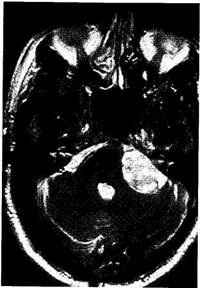

Ранним проявлением невриномы является одностороннее постепенное снижение слуха вплоть до глухоты. Тугоухость иногда развивается незаметно для больного, и ее обнаруживают случайно, когда слух уже отсутствует. Нередко у больного диагностируют одностороннюю нейросенсорную тугоухость, и в течение 5—6 лет он продолжает сохранять трудоспособность. Во всех подозрительных на невриному случаях необходимо делать КТи МРТ (рис. 7.11).

Рис. 7.11. Магнитно-резонансная томограмма. Невринома пред-дверно-улиткового нерва.